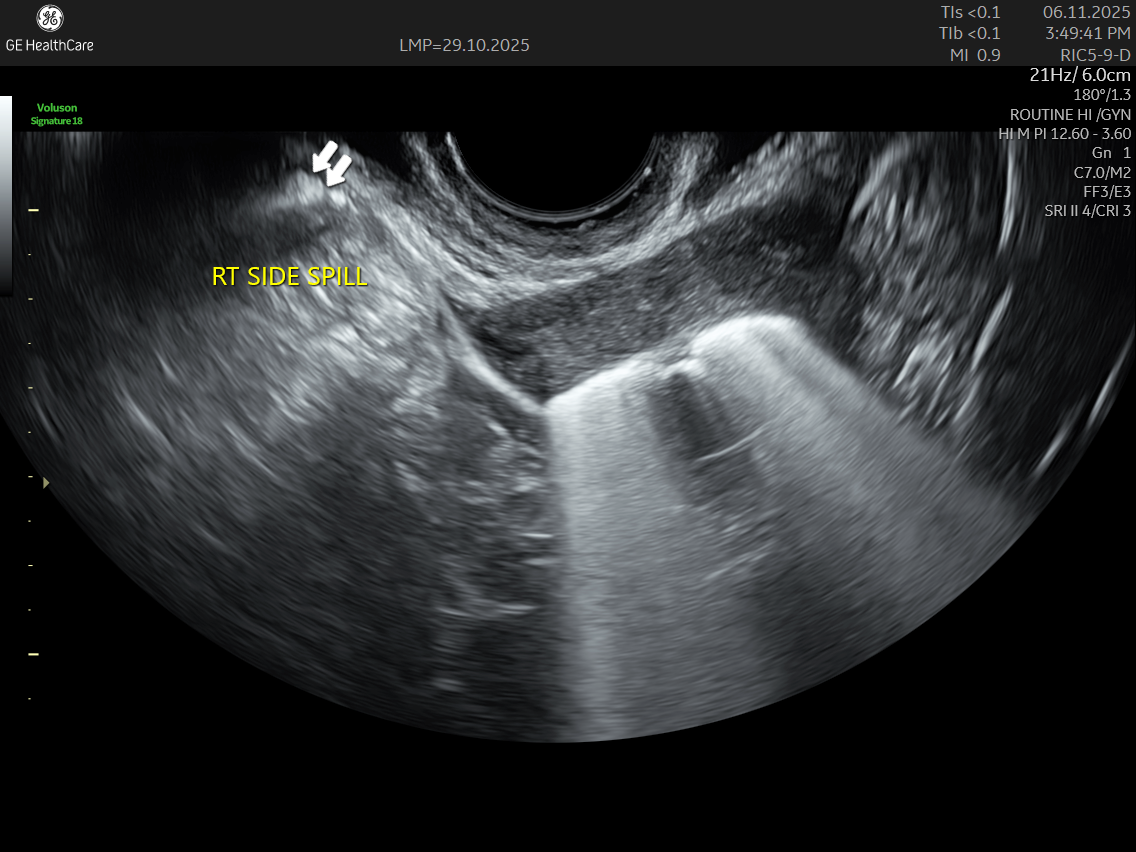

IMAGE GALLERY

Both SIS and SSG are technically the same procedure.. They are a form of advanced ultrasound where sterile saline (SIS) or contrast (SSG) solution is introduced into the uterus to clearly assess the uterine cavity and detect conditions like polyps, fibroids, or anomalies.